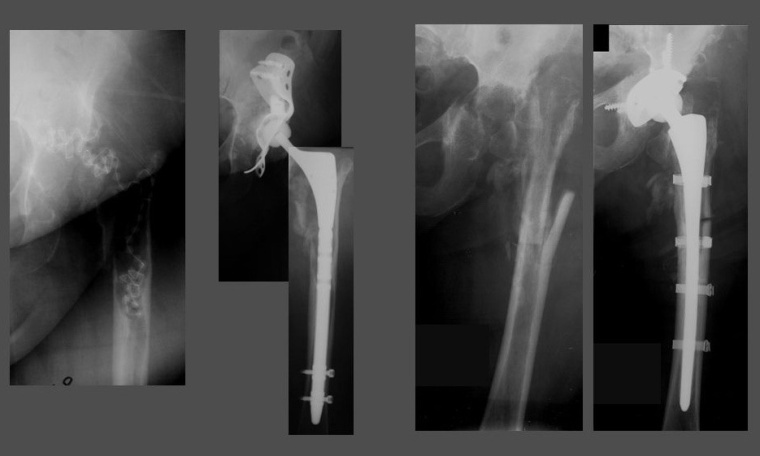

Standardschäfte oder Monoblock-Revisionsschäfte erlauben in nur sehr begrenztem Umfang die Adaptation an diese Bedingungen. Sie erfordern in der Regel eine distale Fixierung, ermöglichen nur eine inkomplette Füllung der Defekte, Offset und Anteversion sind nicht variabel und die Beinlängenadaptation limitiert (Abb. 1a, b).